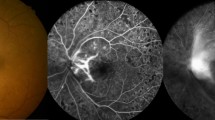

The CFT was measured by SD-OCT (Heidelberg Spectralis HRA+OCT) at each time point (Fig. 2). Visual acuity was measured using the Snellen chart and was converted to logMAR.

Schematic illustration of paper-based ELISA for VEGF detection.

In the clinical setting, patients receive standard-of-care procedures: slit lamp, SD-OCT, and FAG (left panel). Paper-based ELISA requires 1 μL of aqueous humor before operation, and quantification of VEGF concentrations requires 40 μL (right panel). Further colorimetric results can be obtained using a scanner or smartphone. Ophthalmologists can determine treatment according to VEGF concentrations and SD-OCT results.